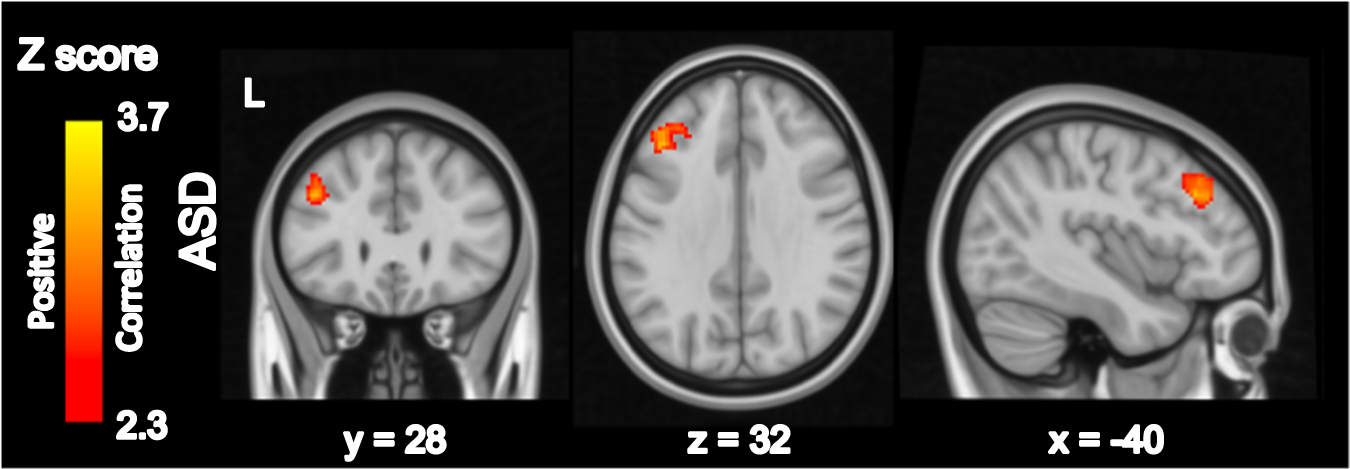

Fig. 3: Somatosensory Cortex Connectivity Related to SSC Glx/Cr.

Whole-brain resting-state analysis using bilateral precentral gyrus seed with Glx/Cr as a bottom-up regressor. Within-group and between-group contrasts were thresholded at Z > 2.30 and cluster corrected at p < 0.05 (see eFig. 3.B for unthresholded maps), only within ASD demonstrated a significant relationship with Glu/Cr. ASD Autism spectrum disorders, L Left.